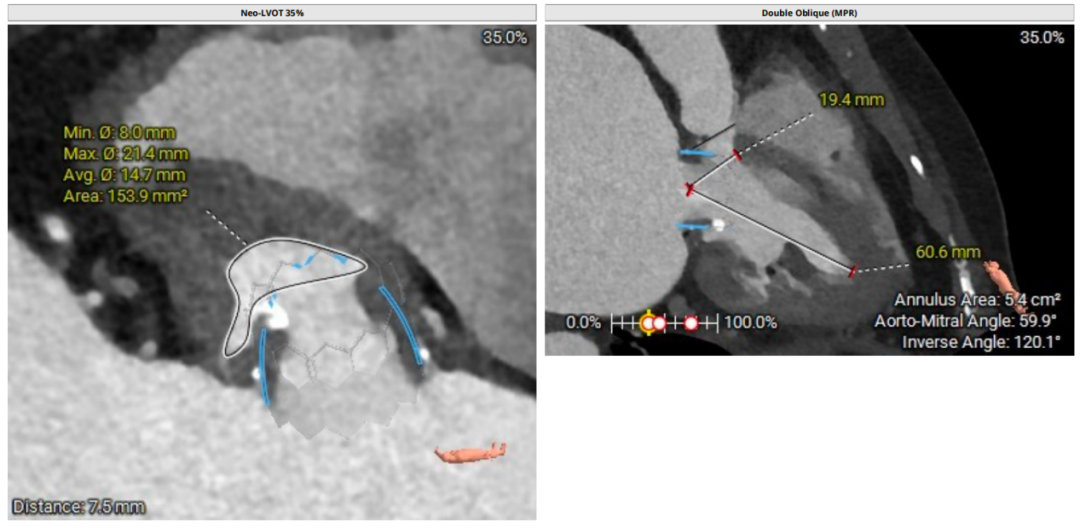

二尖瓣生物瓣支架内径 26.5mm,结合瓣架形态、瓣架高度及手术记录,符合EPIC 27#。瓣中瓣治疗考虑选择25# 介入瓣膜。模拟25# 瓣膜植入,测得NEO-LVOT 面积155.8mm²,术后存在新流出道梗阻风险。左心耳尖端未见血栓。左心房增大73.4*118.7mm,房间隔未见增厚,未见明显钙化,靠后靠下房间隔穿刺点距二尖瓣水平高度27.7mm,房间隔穿刺点高度可。